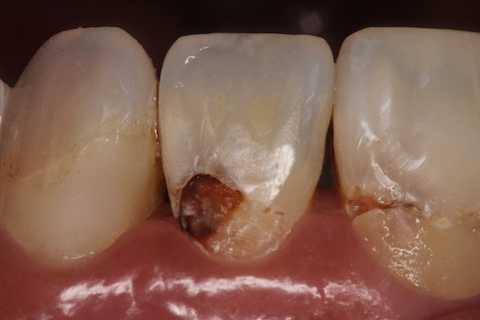

40代女性、右上2、自発痛-

かなりひどい虫歯で、外側表面のエナメル質はなんとか残したが、ペラペラだ。

スプーンエキスカベータで軟化象牙質を剥がすと簡単に露髄した(黄色矢印)。

ひどい虫歯ほど麻酔は要らない。健全な象牙質は削ったり、それどころかエアーを吹きかけたりするだけで痛いのだが、このような健全ではない象牙質は痛くない。露髄して出血しても痛くない。